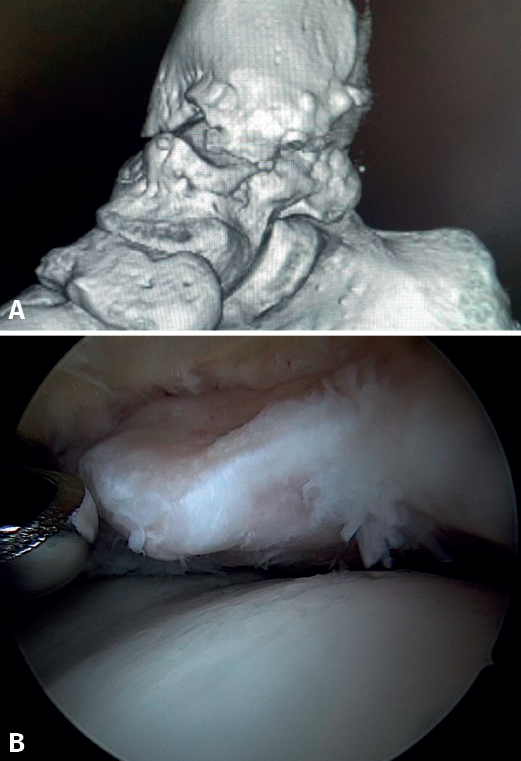

Bony AAI due to osteophytes has also been linked to the presence of chronic instability. It has been postulated that altered joint kinematics secondary to ligament insufficiency favors the development of osteophytes in the anterior region of the tibia and talus(36,37). Recent studies have questioned the theory of repeated capsular traction as the origin of osteophytes in sports(38), as it is easily demonstrated that osteophytes are located intra-articular within the capsular insertion, in the context of ankle arthroscopy (Figure 2). Therefore, ankle dorsiflexion arthroscopy is essential to safely resect osteophytes without damage to the capsule or overlying structures, whereas the classical traction technique (invasive or otherwise) would make resection extremely difficult, and is thus not recommended nowadays for routine use(3,39). Vega distinguished between two types of osteophytes(3), according to whether they are caused by repetitive trauma (peak-shaped) or instability (visor-shaped). The concept of micro-instability is associated with repetitive micro-trauma, which could be the origin of osteophytes with this characteristic morphology (Figure 3).

Resection of the osteophyte is performed by displacing from the top, and gradually reducing it until the joint zone is reached (Figure 2). A basket forceps can be used to resect the area closest to the joint (Figure 5). It is often useful to exchange the viewing and working portals in order to visualize and completely resect the osteophytes. In the case of soft tissue impingement, a 3.8 or 4 mm synoviotome is usually sufficient. The vaporizer is useful in the case of compact impingements, typical of post-traumatic conditions or re-interventions, and also for delimiting the bony part of the osteophyte before resection.